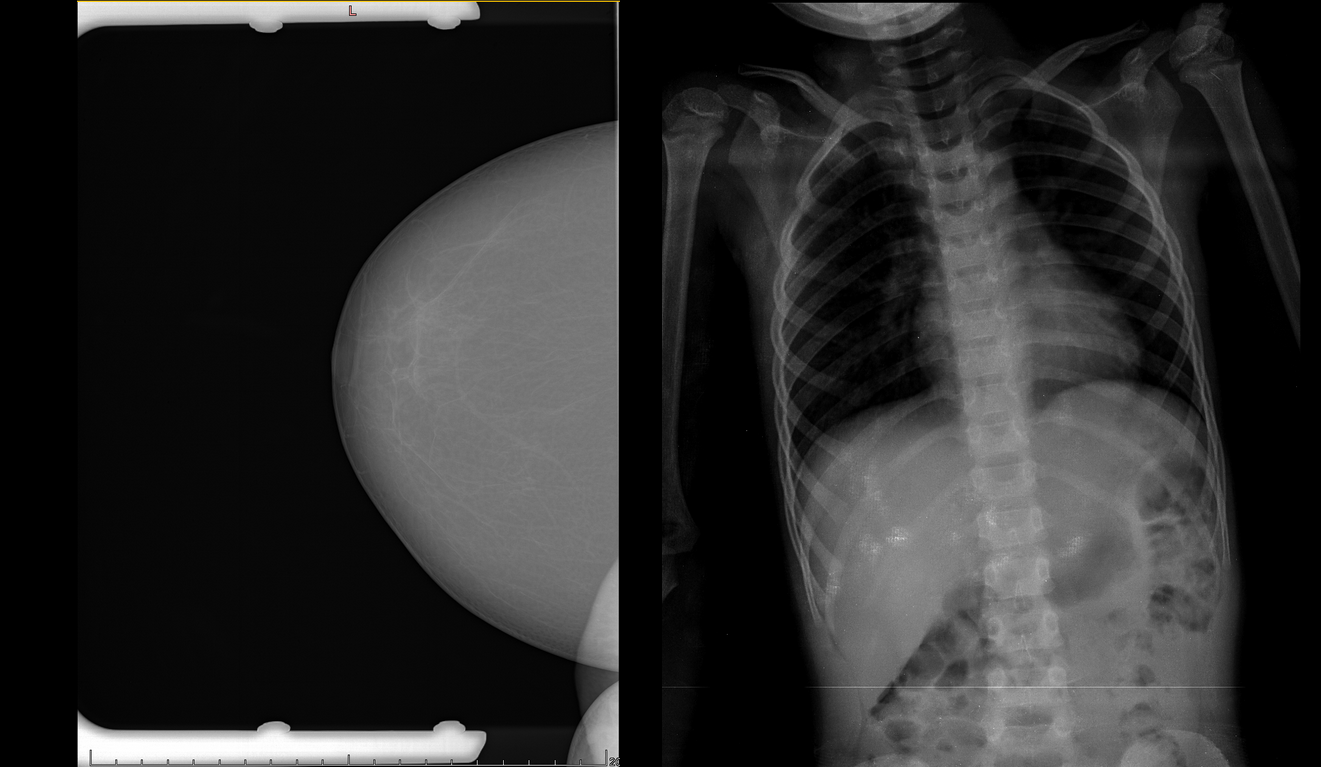

К примеру, неправильно заполненный тег части тела в DICOM-файле и некорректная работа модели по фильтрации снимков может привести к возникновению пневмоторакса в стопе: